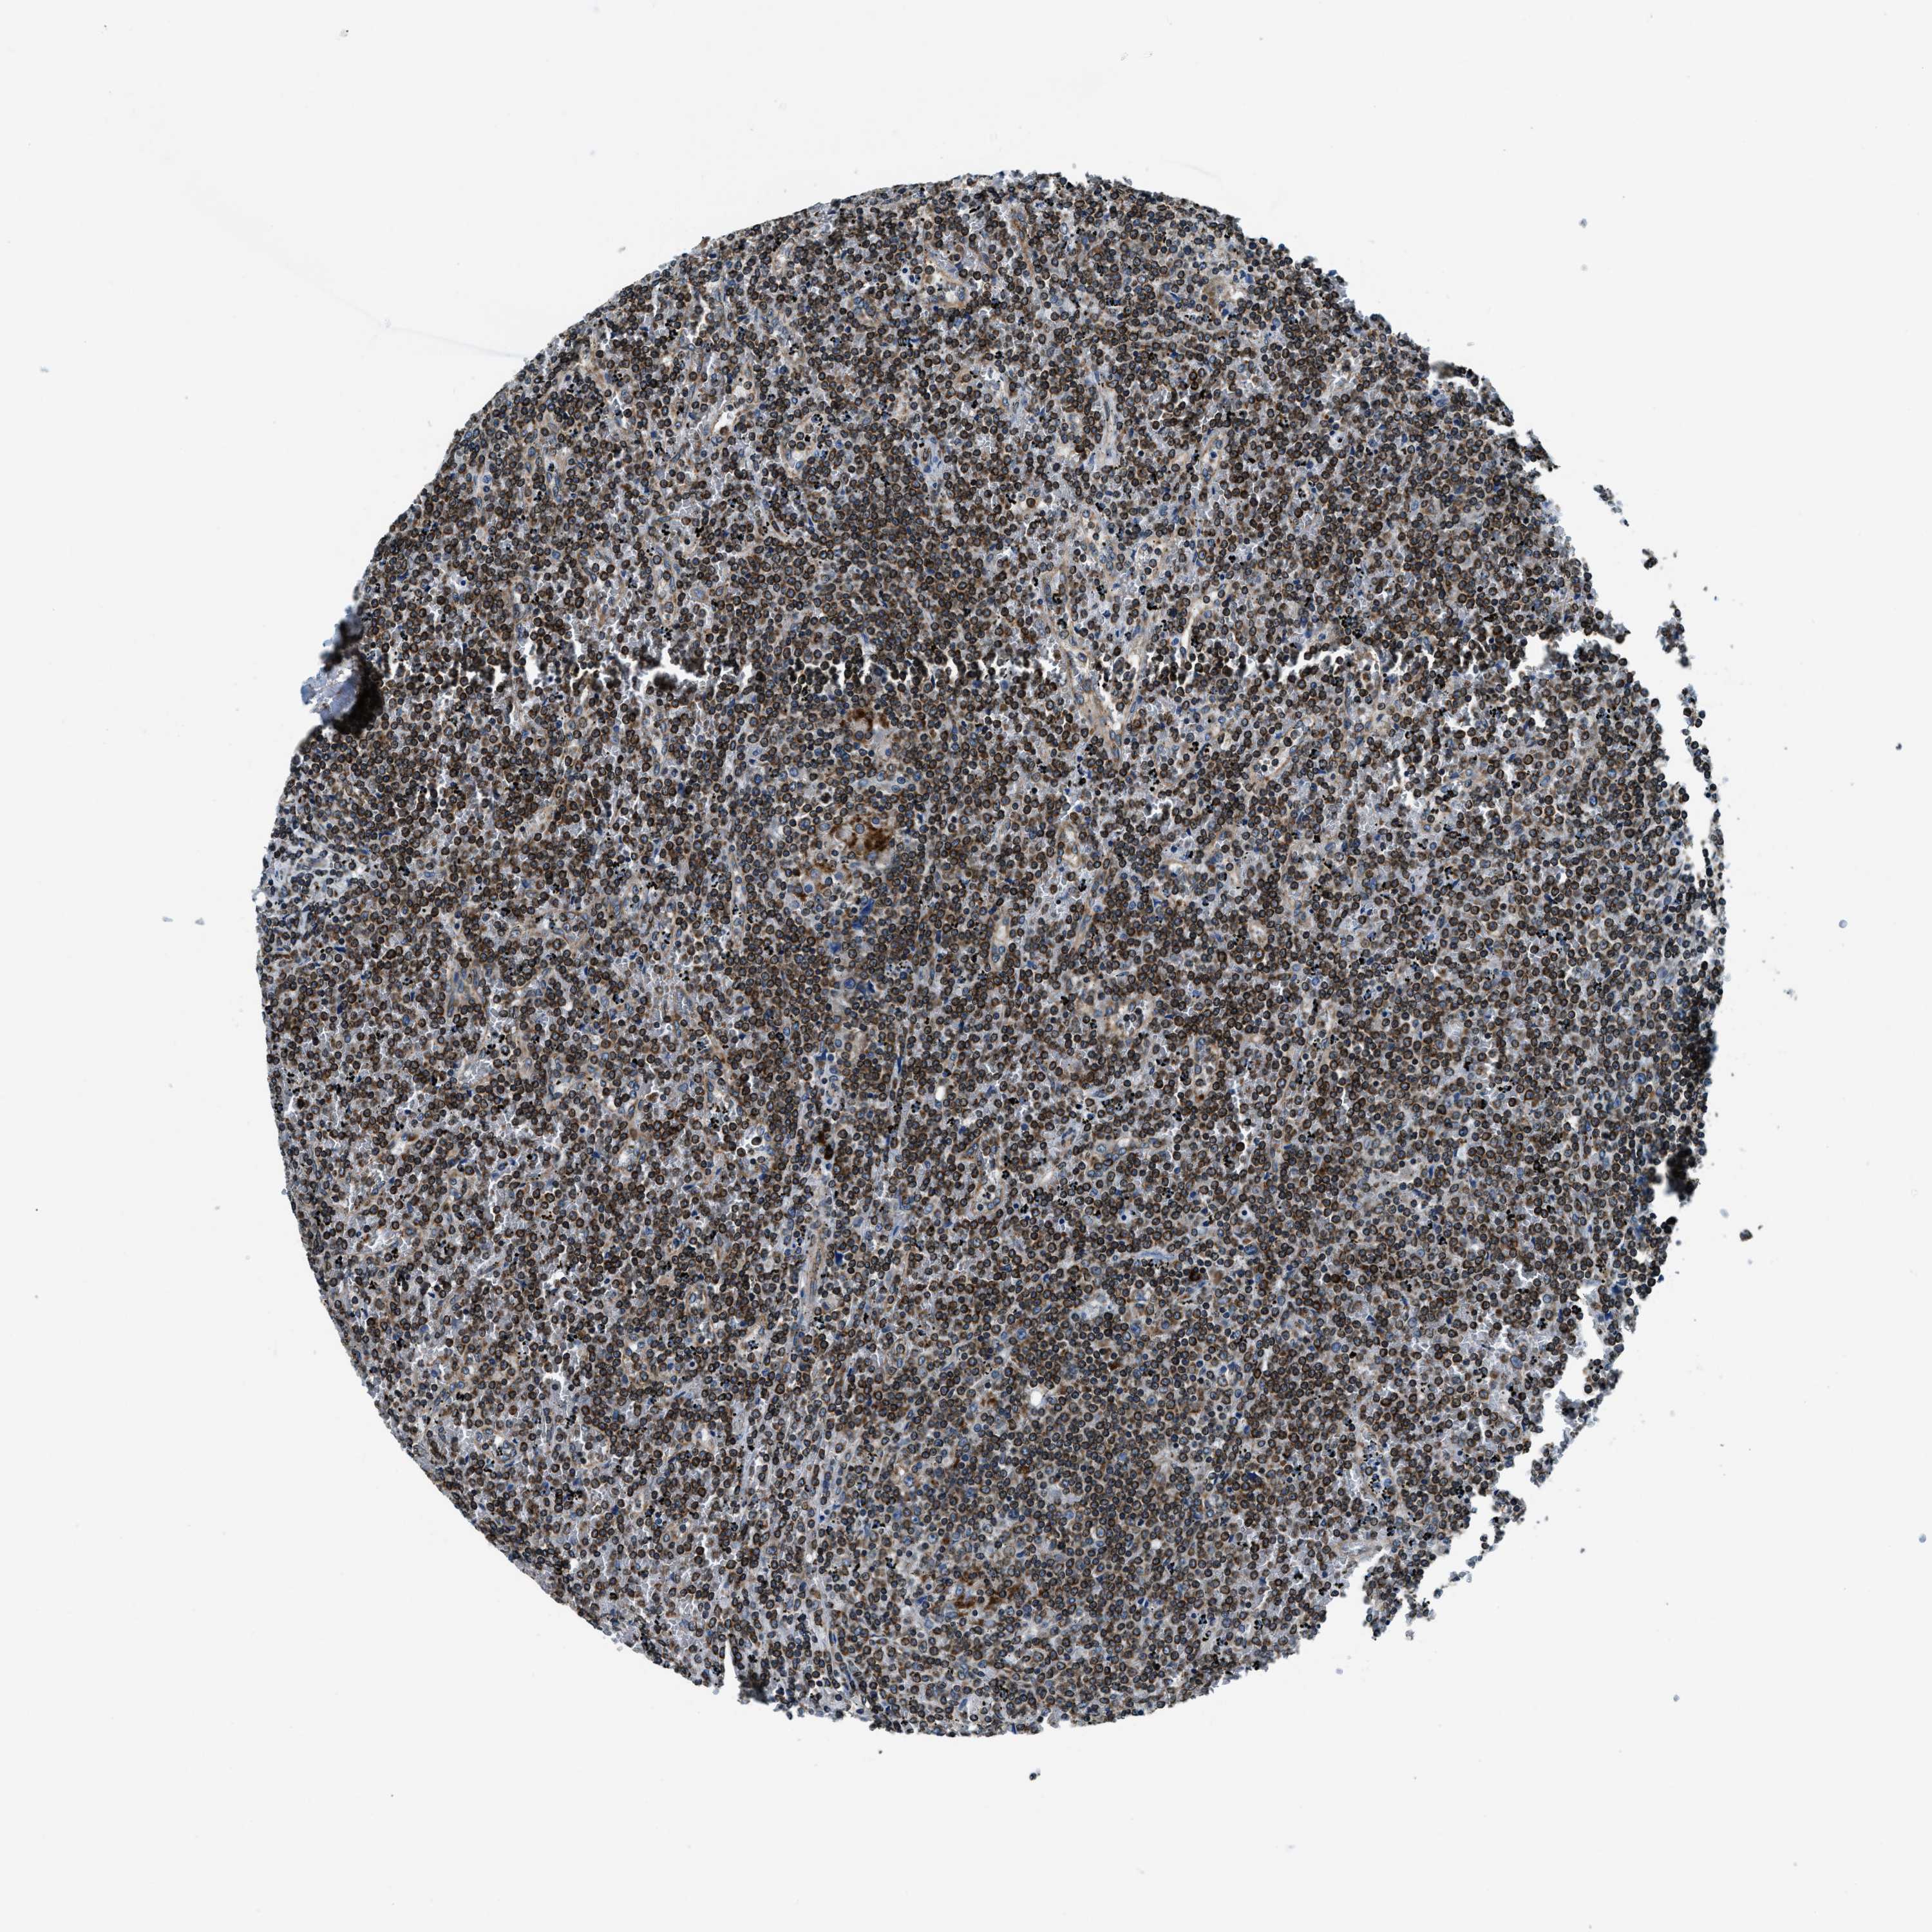

LYMPHOMA - Protein expressioni

A mouse-over function shows sample information and annotation data. Click on an image to view it in a full screen mode. Samples can be filtered based on level of antibody staining by selecting one or several of the following categories: high, medium, low and not detected. The assay and annotation is described here.

Each image is clickable and will lead to virtual microscopy that enables deeper exploration of all samples and also displays staining intensity scores, fraction scores and subcellular localization as well as patient and tissue information for each sample.

Antibody HPA019698

Staining

Medium

Intensity

Weak

Quantity

<25%

Location

Cytoplasmic/membranous

Hodgkin's disease, NOS

Malignant lymphoma, non-Hodgkin's type, High grade

Malignant lymphoma, non-Hodgkin's type, Low grade